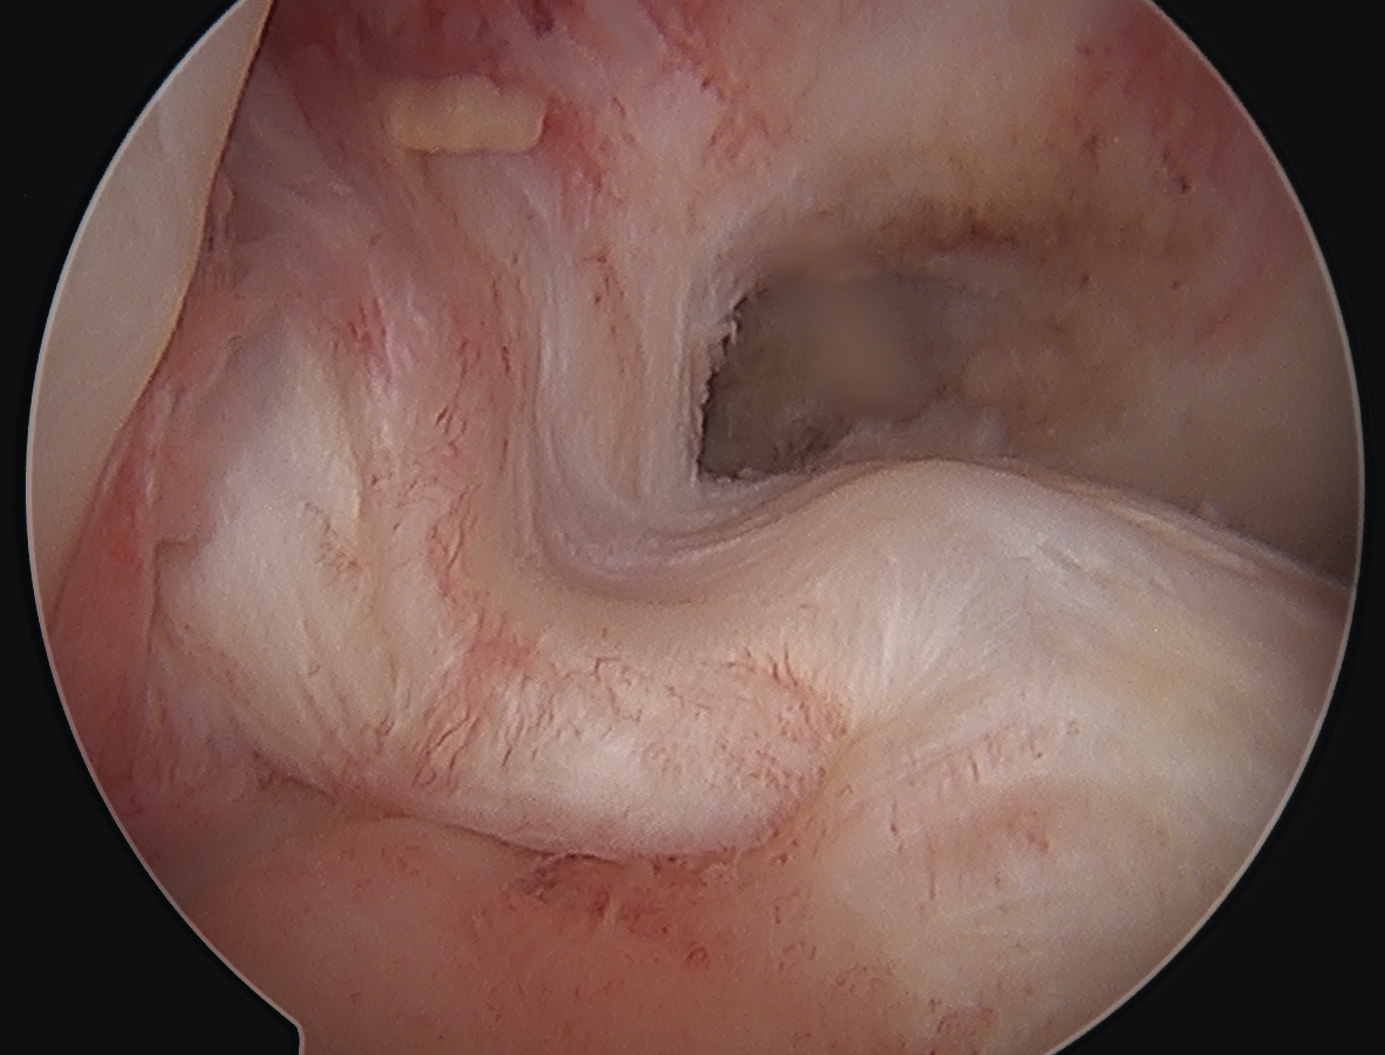

Arthroscopy

May miss tear as is extra-synovial

Chronic PCL tear from femur

Acute PCL femoral avulsion

Apparent ACL laxity due to PCL tear and posterior tibial sag; ACL tension restored with anterior drawer